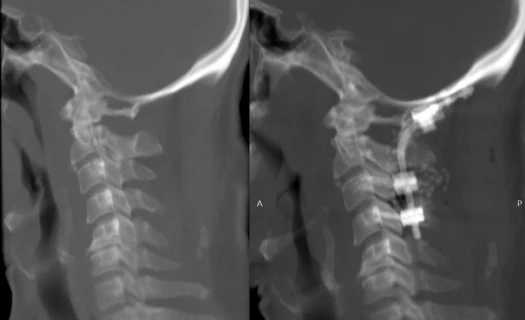

ފުރަތަމަ ފަހަރަށް އައިޖީއެމްއެޗްގައި އޮކްސިޕިޓޯ-ސަރވިކަލް ފިއުޝަން ސާޖަރީއެއް ހަދައިފި